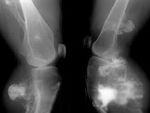

骨膜性软骨瘤是软骨瘤的一种,发生于骨表面、骨膜下、肌腱和韧带附着处的软骨瘤,可见于从儿童到成人的各个年龄组,位于长骨的骨干或干骺端区域,好发于肱骨近端。